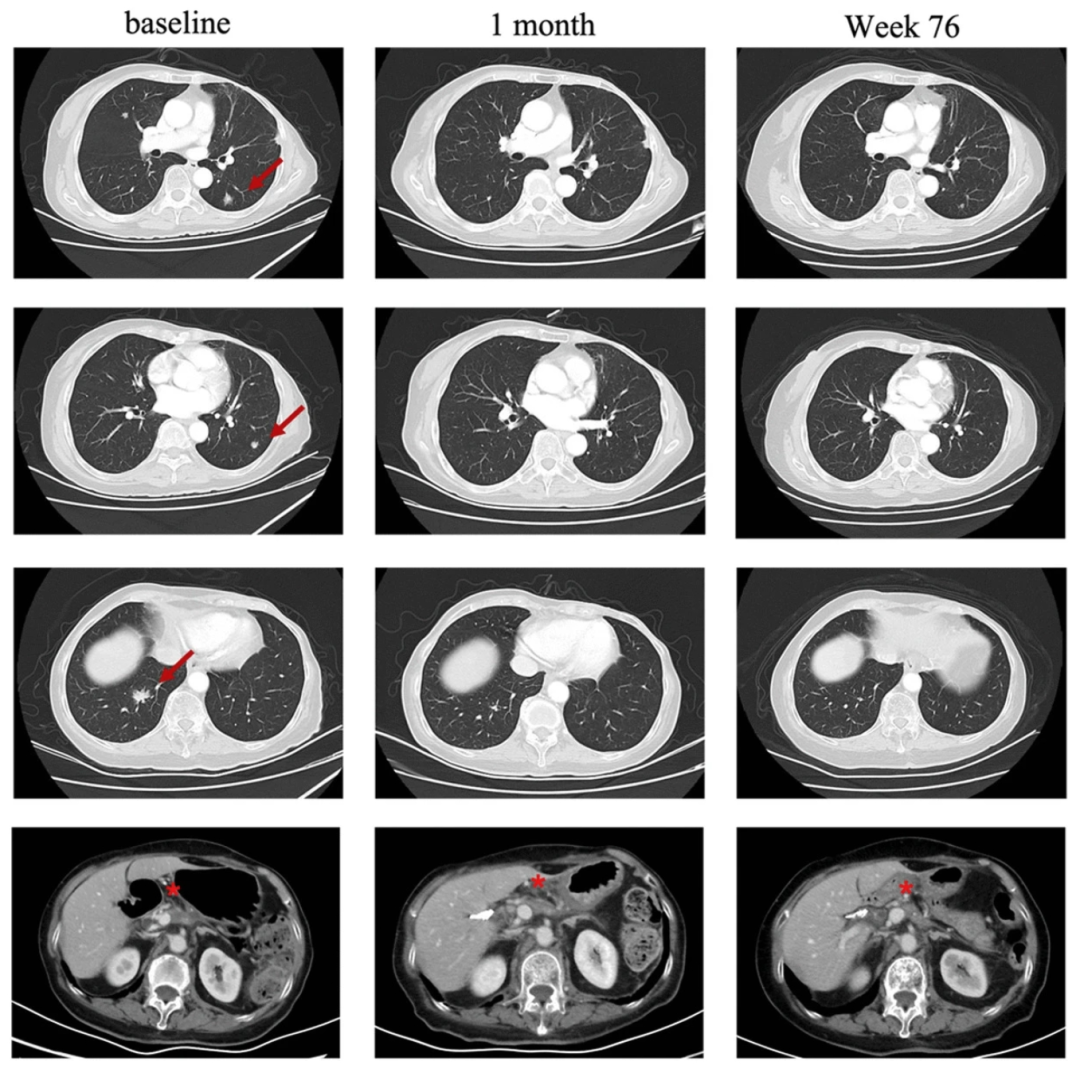

图1患者治疗前后肺部病变的放射学评估

注:“红色箭头”表示“目标病变”。“★”表示“原发病变”

《血液学与肿瘤学杂志》公布了“CT041治疗胰腺癌因CA19-9升高且存在胰腺病变,于2019年5月6日接受手术,病理诊断为pT2N0胰腺癌。5个月后常规术后随访发现肺转移。自2019年12月6日起,一线化疗采用S-1单药治疗。在手术区姑息放疗期间,观察到肺部肿瘤进展。

由于CLDN18.2表达确定为3+/60%,故患者入组CT041临床试验。入组后,患者现接受了淋巴细胞清除治疗,之后回输CT041。治疗后4周初次评估,就达到部分缓解(PR),肺转移靶病灶随后消失并达到完全缓解。直到2023年7月最后一次随访时,肿瘤仍控制良好。